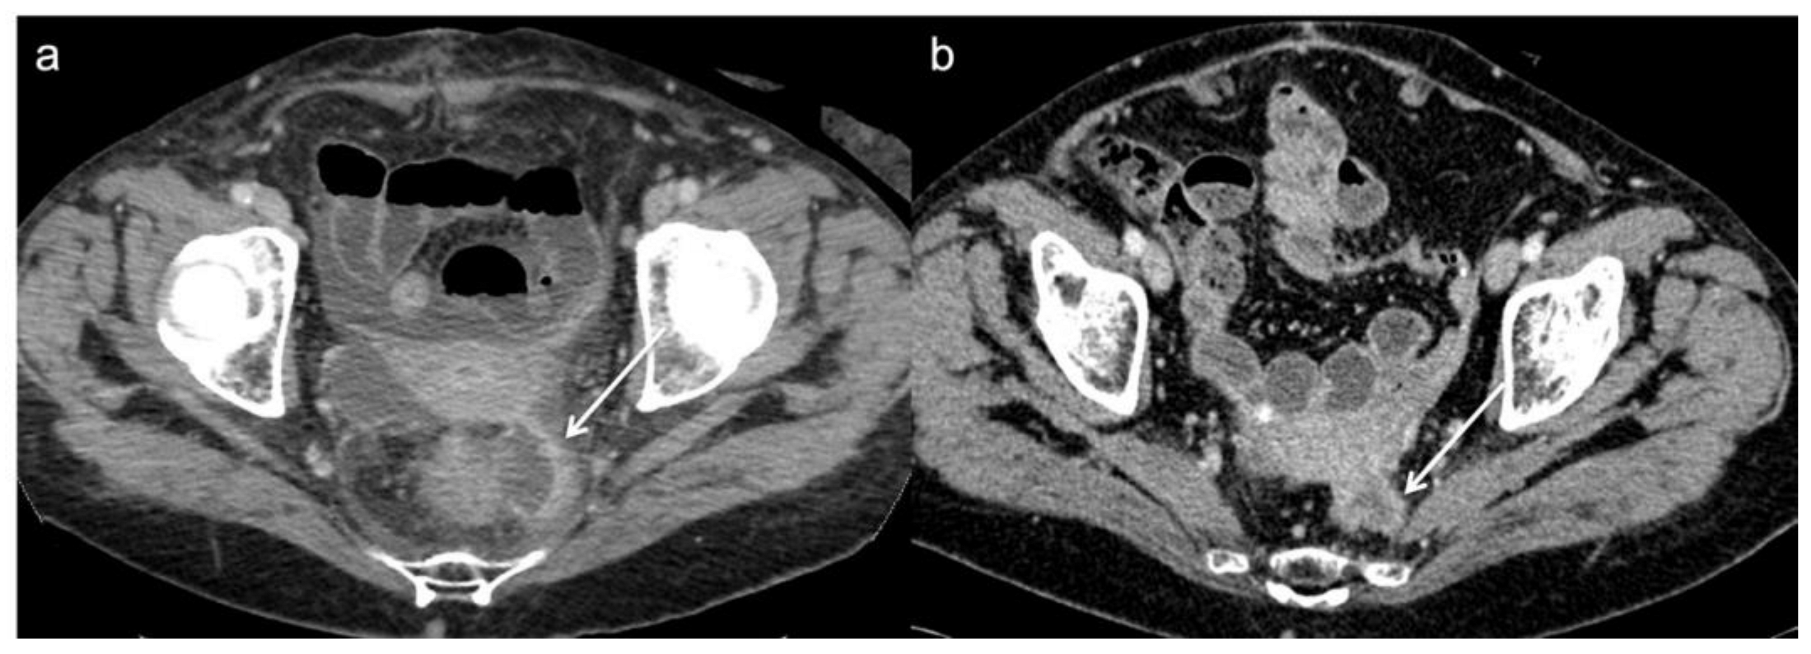

- Molinelli, V.; Angeretti, M.G.; Duka, E.; Tarallo, N.; Bracchi, E.; Novario, R.; Fugazzola, C. Role of MRI and added value of diffusion-weighted and gadolinium-enhanced MRI for the diagnosis of local recurrence from rectal cancer. Abdom. Radiol. 2018, 43, 2903–2912. [Google Scholar] [CrossRef] [PubMed]

- Torricelli, P.; Pecchi, A.; Luppi, G.; Romagnoli, R. Gadolinium-enhanced MRI with dynamic evaluation in diagnosing the local recurrence of rectal cancer. Abdom. Imaging 2003, 28, 19–27. [Google Scholar] [CrossRef] [PubMed]

- Lambregts, D.M.J.; Cappendijk, V.C.; Maas, M.; Beets, G.L.; Beets-Tan, R.G.H. Value of MRI and diffusion-weighted MRI for the diagnosis of locally recurrent rectal cancer. Eur. Radiol. 2011, 21, 1250. [Google Scholar] [CrossRef] [PubMed]

- Colosio, A.; Soyer, P.; Rousset, P.; Barbe, C.; Nguyen, F.; Bouché, O.; Hoeffel, C. Value of diffusion-weighted and gadolinium-enhanced MRI for the diagnosis of pelvic recurrence from colorectal cancer. J. Magn. Reson. Imaging 2014, 40, 306–313. [Google Scholar] [CrossRef]